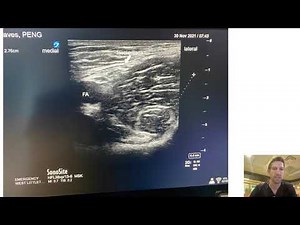

- Peng Block

Ultrasound - Hip Surgery

Types - Hip Block

Procedure - Peng Block

Operation - Peng Block

Ultrasound-Guided Toronto - Hip Repair Surgery